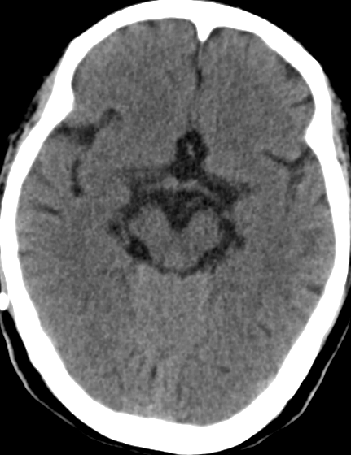

2013-8-8 CT

2013-8-7 脑室腹腔分流术,初压130

2013-8-8 仍诉头痛